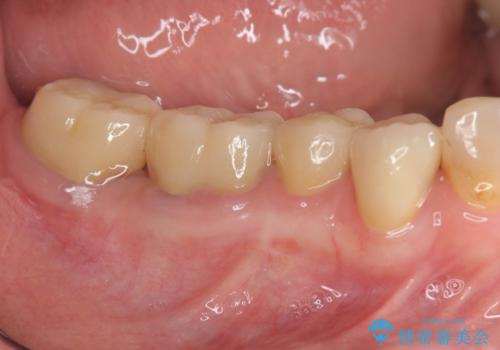

総合歯科治療

インプラント治療&セラミック治療掲載症例数197件

根管治療&セラミック治療掲載症例数205件

歯周病治療&インプラント治療掲載症例数74件

歯周病治療&セラミック治療掲載症例数192件